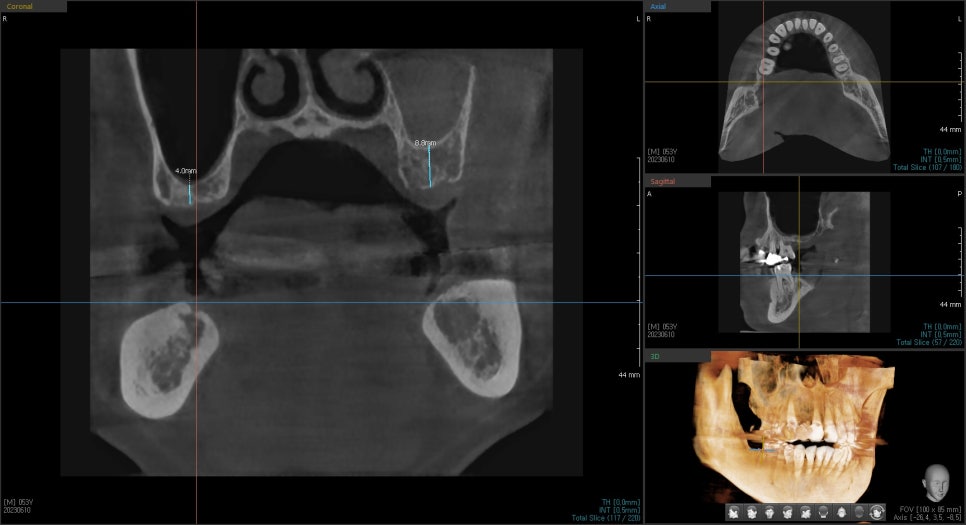

그 이유는 이 환자분의 경우 상악동거상술이 같이 동반되어야 하는 경우로

상악동과의 치조골 높이를 측정하였을 때

왼쪽 위 치아가 오른쪽 치아보다 잔존골 높이가 낮아

상악동거상술을 더 많이 해야 하고

더 오래 기다려야 하기 때문이였는데요.

상악동에 대해서 좀 더 설명드리겠습니다.

상아공이란 두개골과 코 사이에 위치한 빈 공간을 말합니다.

위턱에 임플란트를 심을 경우 상악동도 꼭 같이 정밀체크합니다.

상악동이 크고 뼈의 두께가 얇은 경우, 아래로 내려온 상악동을

위로 올려 임플란트 식립 공간을 충분히 확보해 줘야 합니다.

이 시술을 상악동 거상술이라고 합니다.